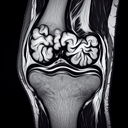

МРТ колінного суглобу

Обстеження МРТ колінного суглоба—це безболісна і неінвазивна процедура, яка використовується для отримання детального зображення структури суглоба. МРТ дозволяє виявити різні проблеми, такі як: - Пошкодження менісків - Травми зв'язок (наприклад, передньої хрестоподібної зв'язки) - Запальні процеси - Виявлення пухлин або інфекцій - Оцінка стану хряща і кісткових структур Медичний центр "Ультрадіагностика" в Хмельницькому пропонує високоякісні послуги МРТ, які проводяться на сучасному обладнанні з високою роздільною здатністю. Це дозволяє лікарям точно діагностувати проблеми і розробити ефективний план лікування...